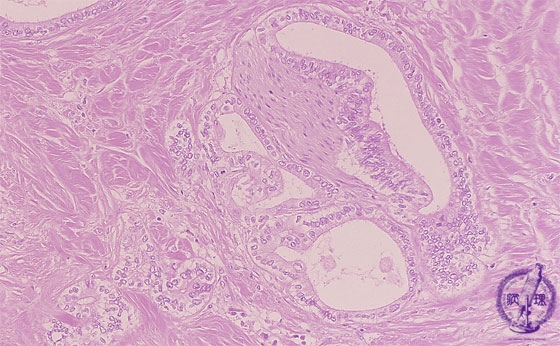

- ★(13)Intrahepatic bile duct cancer (adenocarcinoma)

Microscopic image (HE stain, intermediate power): Neuronal invasion (yellow arrow) by tubular adenocarcinoma is seen.